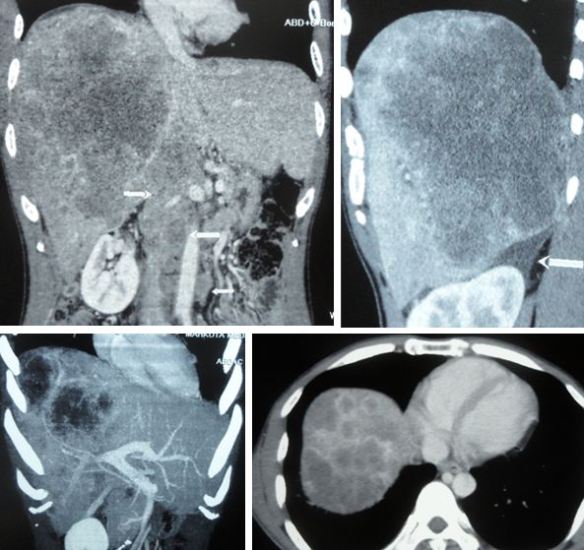

I had a chance to talk to his doctor who told me my brother had anaplastic thyroid cancer. In addition, there were extensive metastases in his lungs and liver. Without doubt – by just looking at the CT scan images (below) – I knew that his days were numbered. No treatment would be able to save him.

On top of this aggressive, rare cancer he also had metastases in his lung and liver. His metastasis was very serious indeed. There is no way anyone can pretend to be a “hero” trying to save him. Added to that was the metastasis to the liver. I was not able to know how extensive it was because I was not able to see the CT scan of his liver.